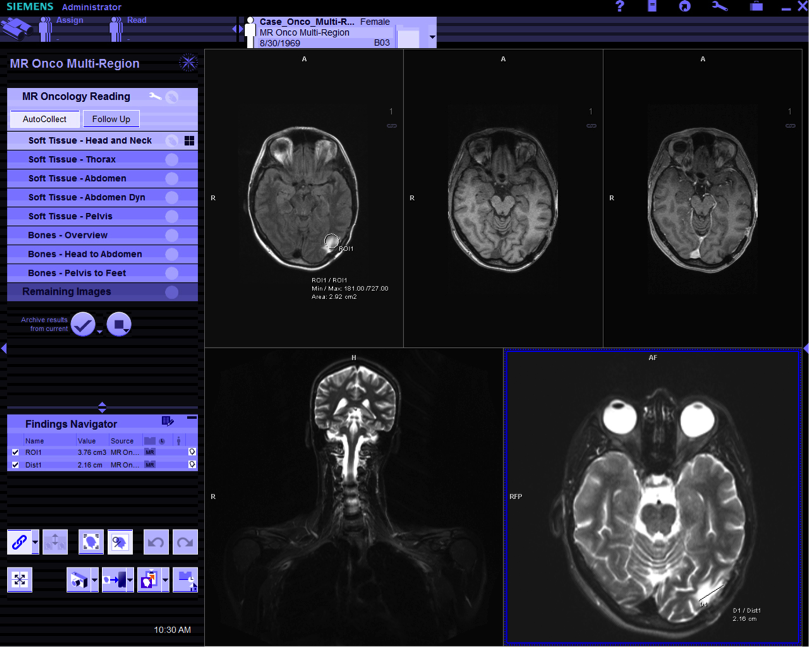

In 1998 I started working as a usability engineer at Siemens’ Corporate Research. One of the business units we were working with was computed tomography (also known as a CT scan) and other medical imaging systems. At this time, Siemens Medical developed Syngo, a unified software for all imaging systems, that featured a visual appearance different from any standard operating system at that time (see Figure 2 for a current example). CT scanners are expensive machines. Customers expect a high-quality industrial design, and Siemens wants clear brand recognition. However, the existing software had an interface developed in OSF/Motif, which was—let me assure you—not the most beautiful sight. Syngo was meant to match the software’s look with the already existing quality of hardware design. To me, it again highlighted that focusing on usability alone may not do the trick.

Figure 2. Siemens Syngo.Via. Source: Siemens Press, www.siemens.com/press, reference number: HIM200911014-03.

The designer working on the visual appearance of Syngo, Axel Platz, of course, took the same line. His argument was that by focusing on usability only, aspects important to him and users alike, such as novelty and beauty, go unnoticed. There is a risk to condemn novel and interesting ideas, just because they produce some minor irritations, when being used for the first time. Obviously, we needed something to more systematically address these kinds of trade-offs.